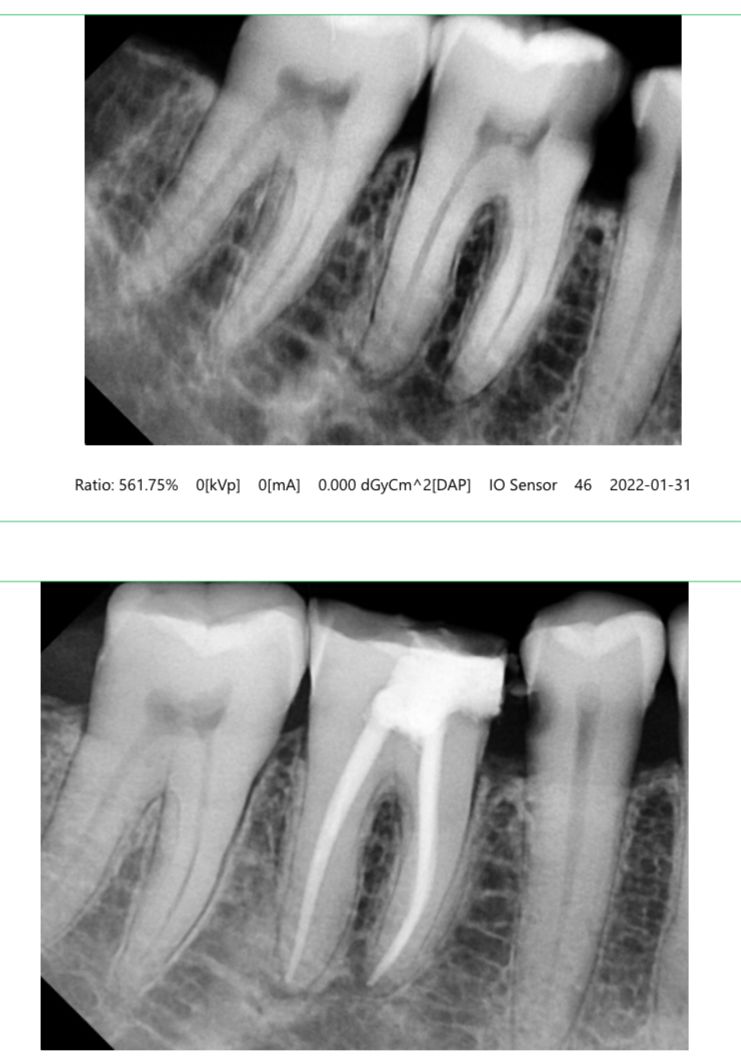

A Root Canal Treatment is a procedure that removes infected or damaged pulp from inside the tooth. It stops pain, prevents extraction, and saves your natural tooth.You may require RCT if you experience:

Procedure Steps:

Diagnosis & X-ray – To identify the infected area.

Cleaning the Canals – Removal of infected pulp and bacteria.

Shaping & Disinfection – Preparing the canals for filling.

Filling the Canal – Sealing with biocompatible materials.

Crown Placement – Recommended for added protection and strength.